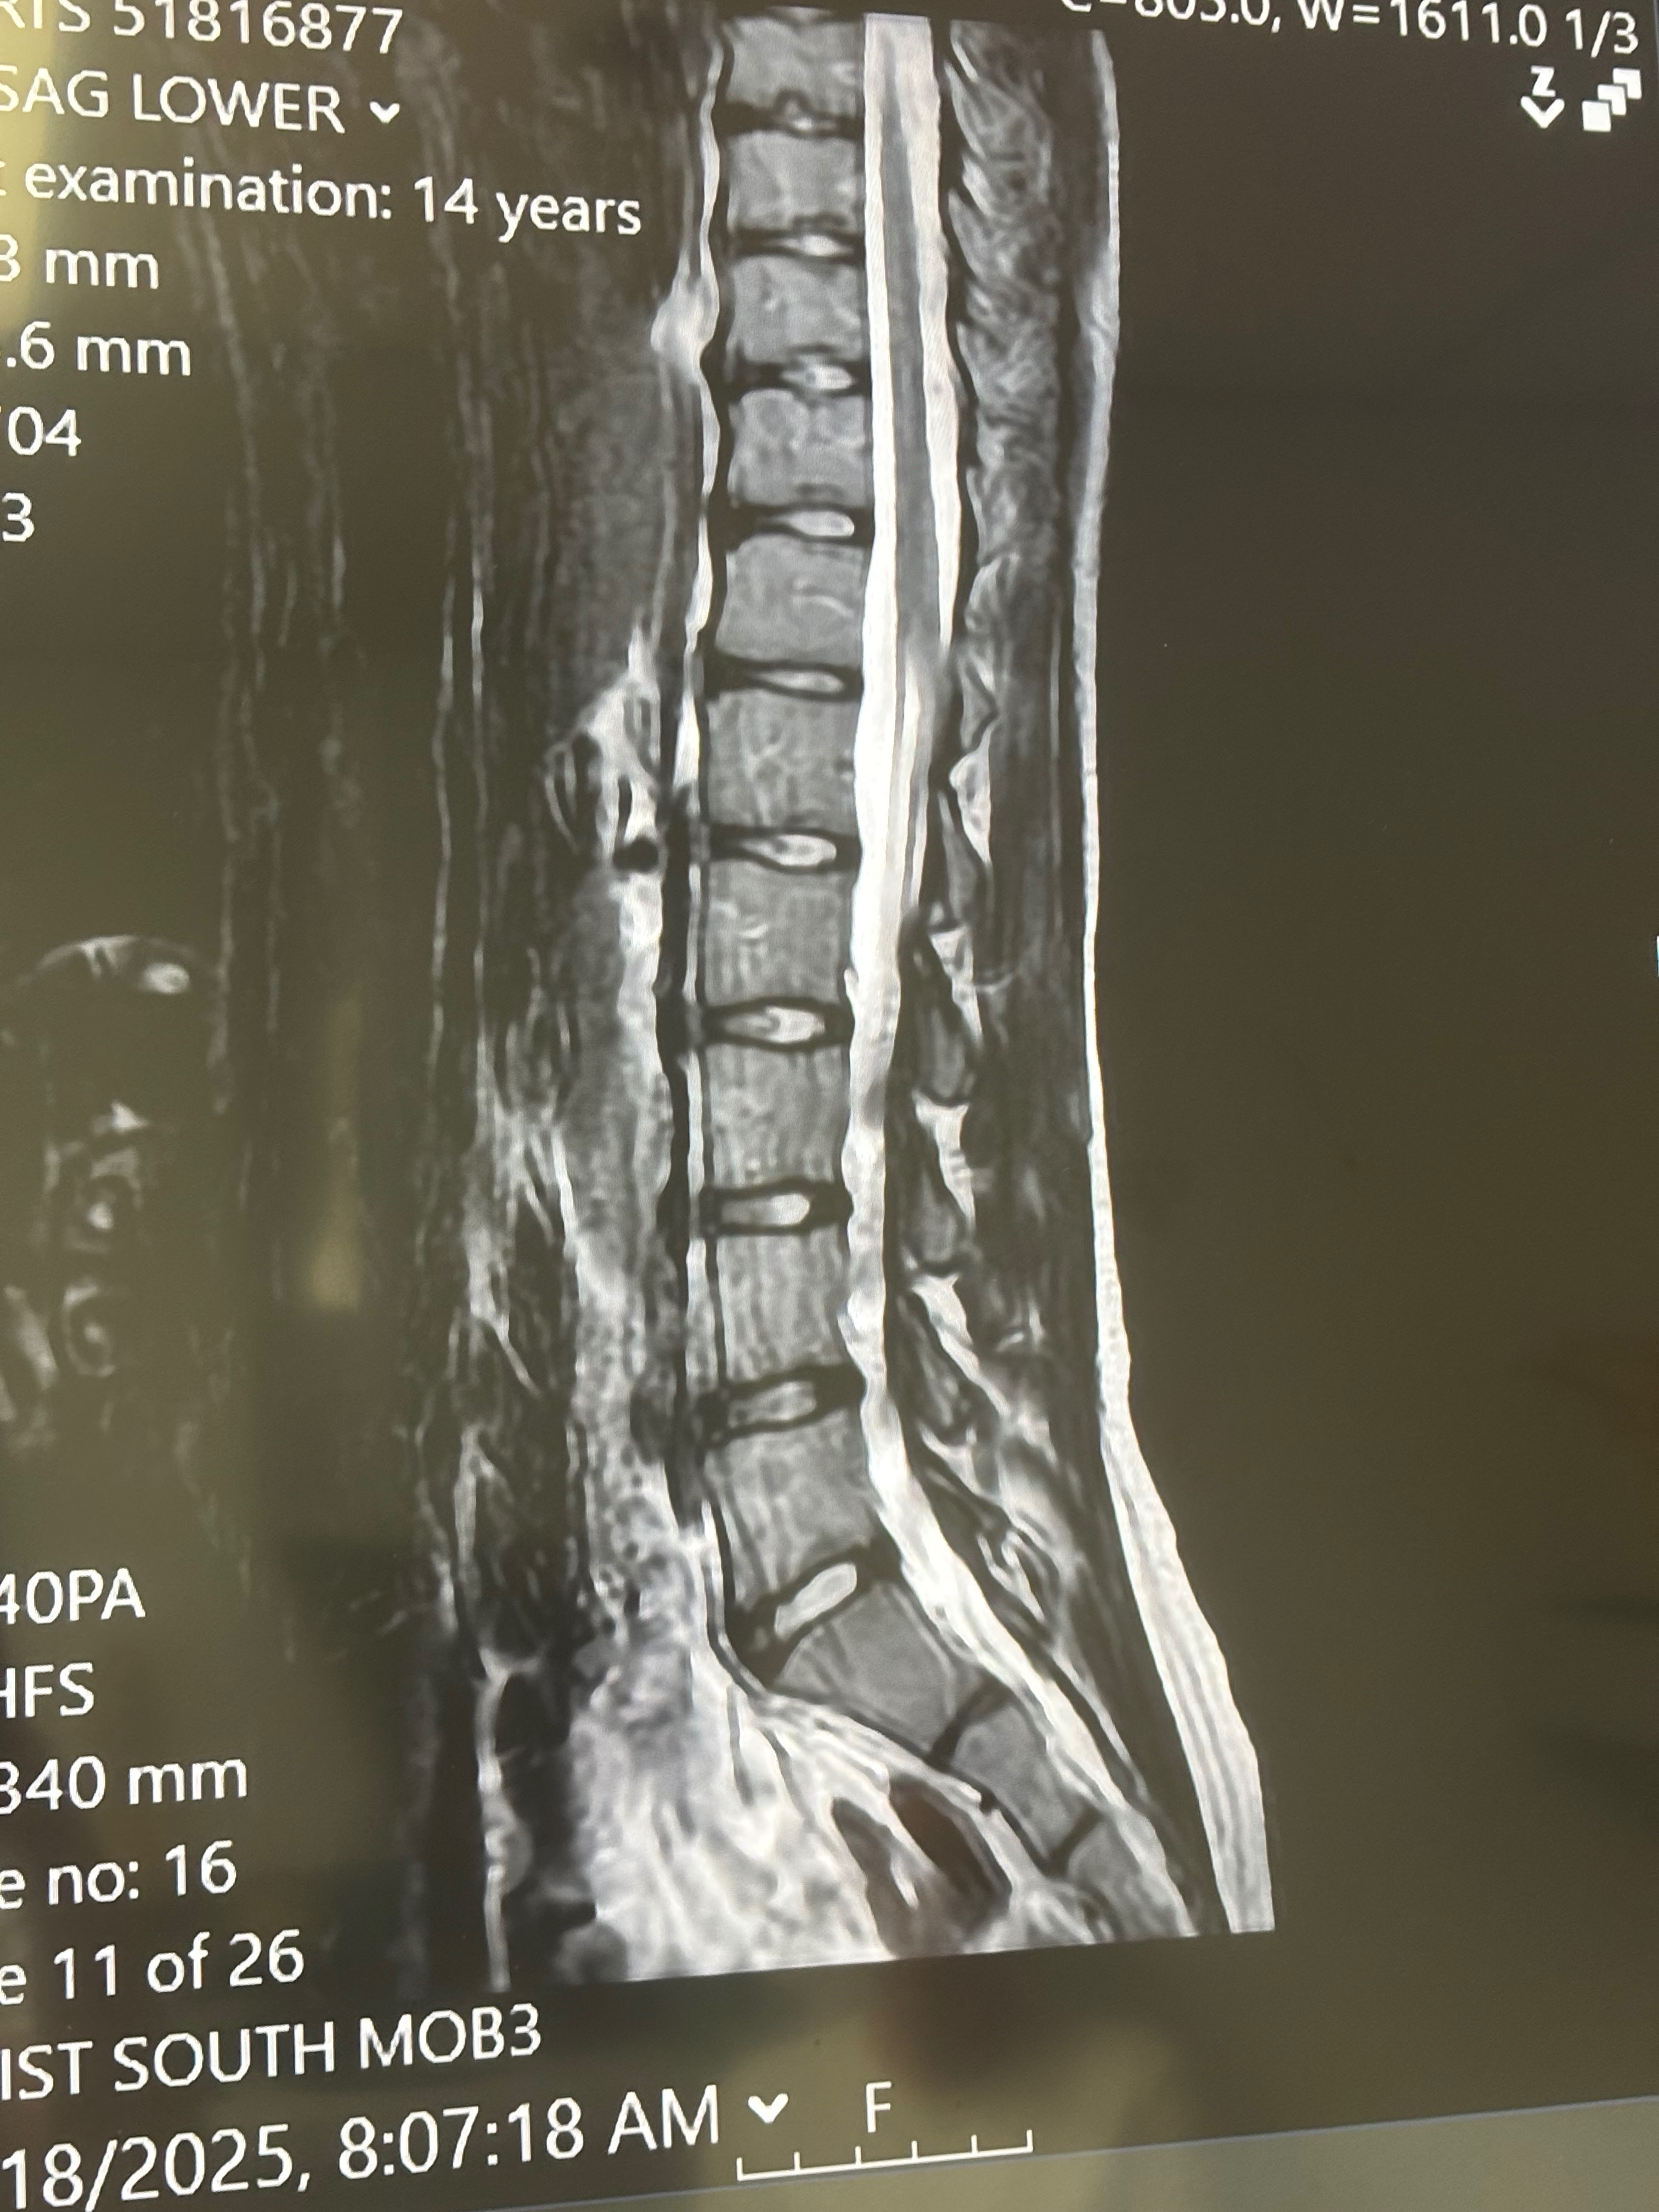

I'm raising money as a 15-year-old teen who has been suffering with chronic back pain . The pain has affected my daily life, can’t even sit still in school, go to the nurse crying. I’ve tried everything in the books, physical therapy, ibuprofen, Tylenol, heat, ice, chiropractors, braces, you name it. After all of that you lose hope I lost hope in a diagnosis and getting seen and heard, it takes a toll on anyone but especially a 15 year old girl. But, after 3 years of struggling, putting money to things that don’t work, multiple doctors with no answer, there was finally ONE who heard my cries and struggles and finally found the answer to my pain and solution but, struggling to pay.

Since we've FINALLY got our answers summer needs surgery and we need your help!